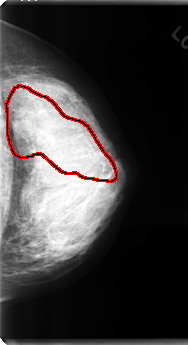

C_0120_1.RIGHT_MLO

FILE: C_0120_1.LEFT_MLO.OVERLAY

TOTAL_ABNORMALITIES 1

ABNORMALITY 1

LESION_TYPE CALCIFICATION TYPE AMORPHOUS-PLEOMORPHIC DISTRIBUTION SEGMENTAL

ASSESSMENT 5

SUBTLETY 5

PATHOLOGY MALIGNANT

TOTAL_OUTLINES 1

BOUNDARY